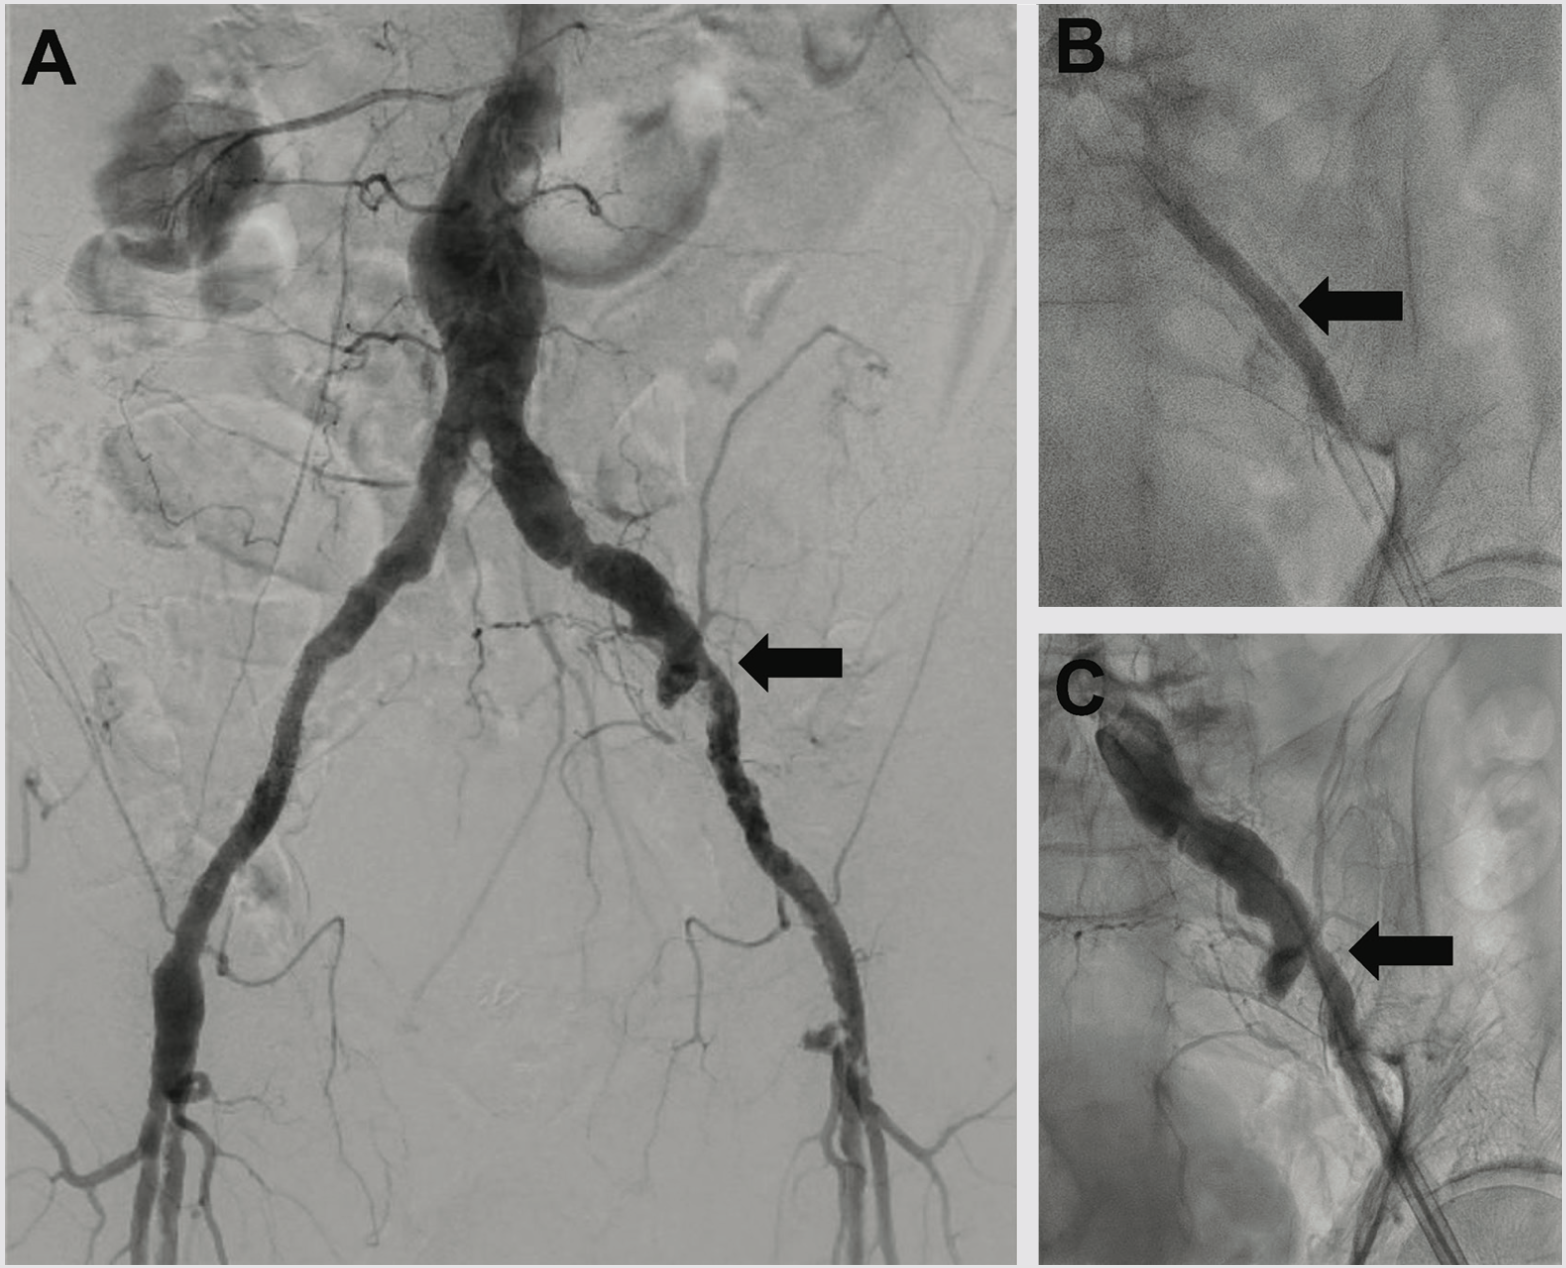

The pre-PCI right heart catherization showed a pulmonary capillary wedge pressure of 26 mmHg with a cardiac index of 2.0 L/min/m2. Because of marginal hemodynamics, we planned Impella (Abiomed)-supported PCI. Radial-to-peripheral iliofemoral angiography demonstrated (1) a patent right iliac stent and common femoral artery patch repair site, and (2) a severe calcific left iliac stenosis (Figure 2). To avoid access issues at the right femoral artery patch repair site, we opted for Impella implantation in the left common femoral artery (LCFA). The Impella sheath would not traverse the left iliac stenosis, so we treated with peripheral Shockwave balloon angioplasty (7.0 mm) (Shockwave Medical) to facilitate Impella placement and achieved an excellent angioplasty result (Figure 2).